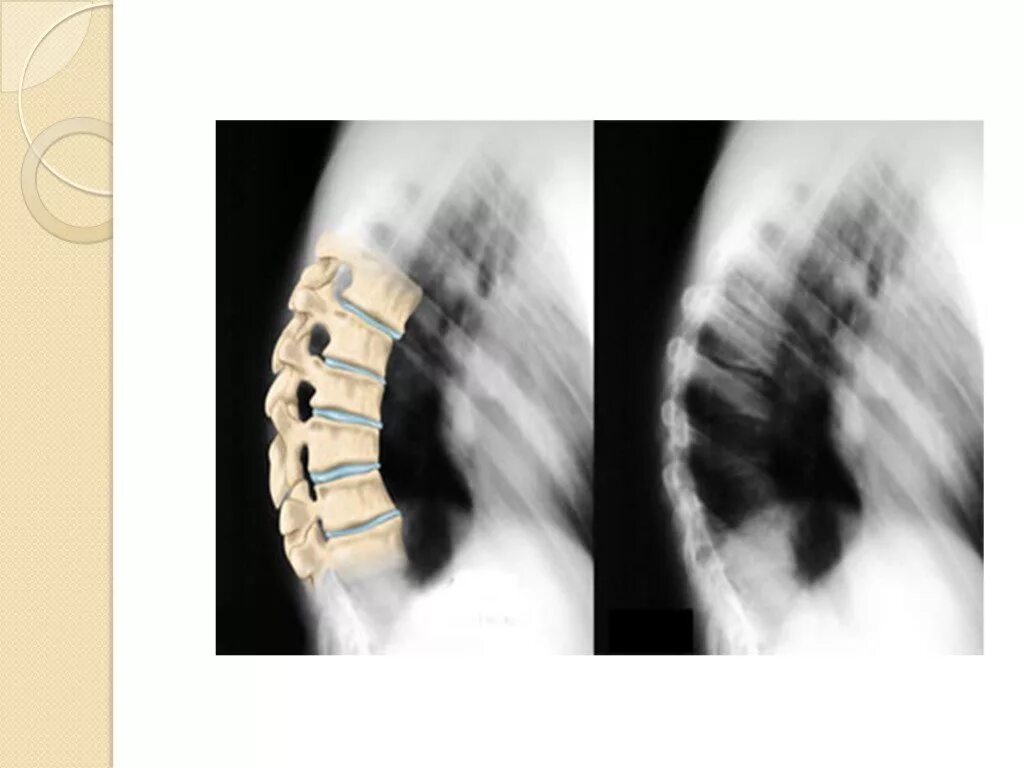

Болезнь шейермана мау что